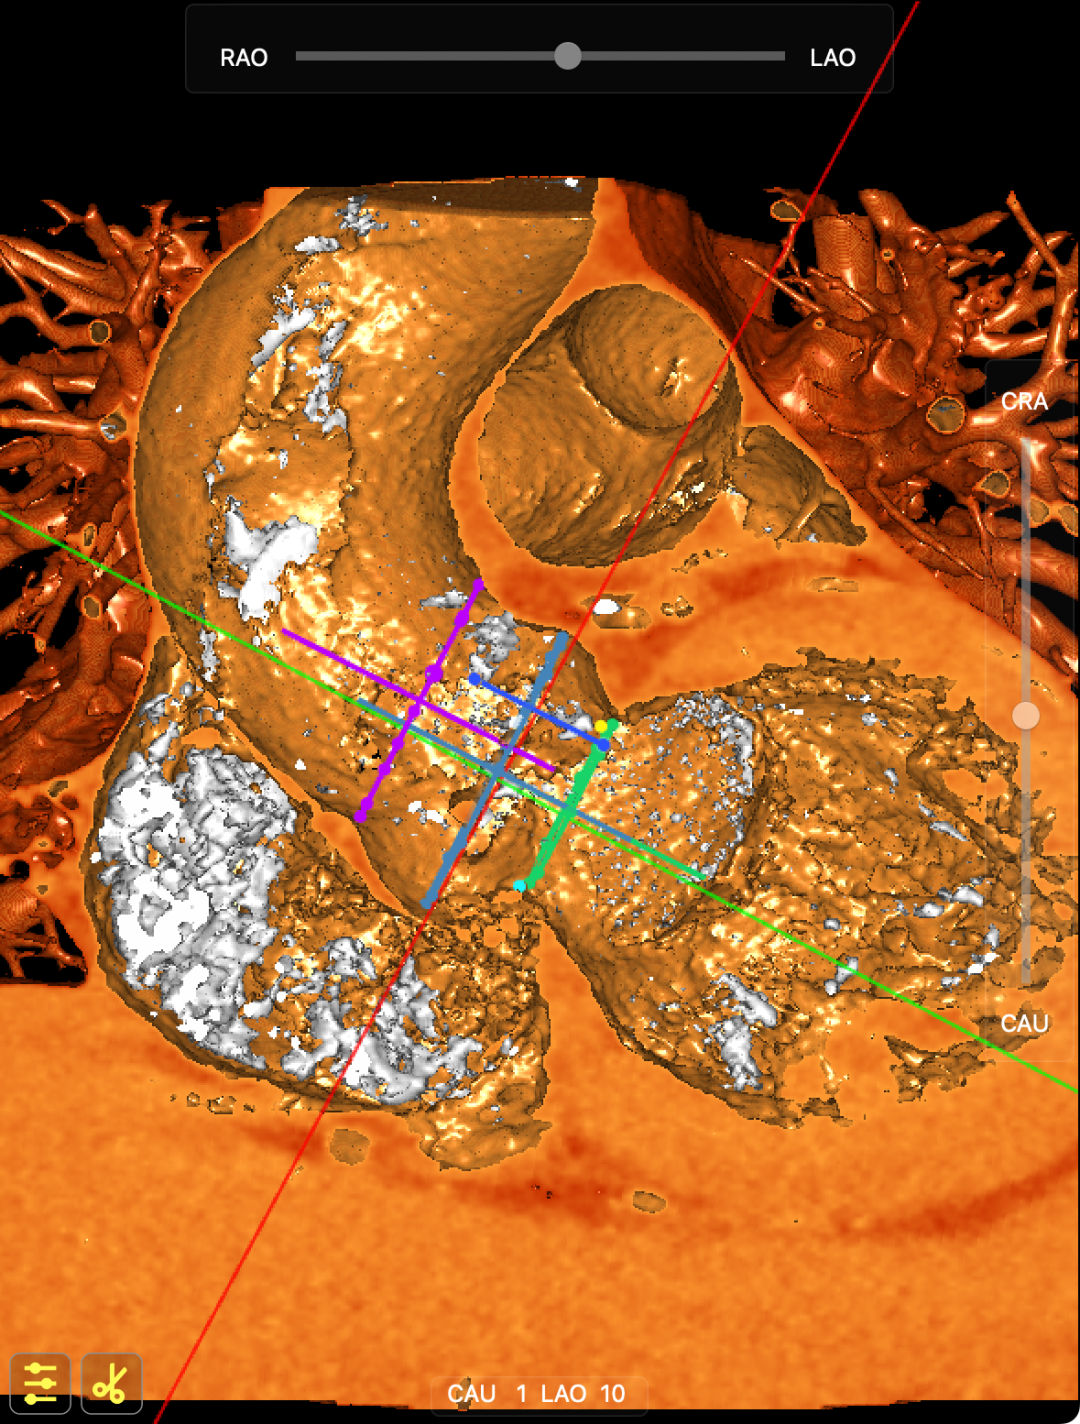

术前CT提示

主动脉升弓降部管不规则增厚并多发钙化,主动脉弓部左锁骨下动脉开口以远瘤样扩张,管径46*43mm。患者主动脉瓣环面积折算直径约26mm。升主动脉管径约32.5mm,降主动脉管径27.5mm;双侧冠脉开口高度可(左冠17.63mm,右冠12.18mm)。头臂血管右侧无名动脉、左侧颈总动脉、左侧锁骨下动脉管壁不规则增厚;头臂干起始部管壁钙化,管腔轻微狭窄。腹主动脉、双侧髂总动脉及其分髂内、髂外动脉管壁不规则增厚并钙化。

CT影像

手术策略

该例患者超声提示主动脉瓣三叶瓣钙化重度狭窄、中度反流,合并基础疾病多,且前不久因急性非ST段抬高型心肌梗死于LAD植入支架,身体状况欠佳,属于外科高危患者。在血管方面,患者存在主动脉弓部动脉瘤,胸、腹主动脉及其分支粥样硬化,在进行手术是需要注意保护血管,避免引发血管相关并发症。经术前CT评估,团队最终选择TruBeta®AV26规格经导管主动脉瓣瓣膜。